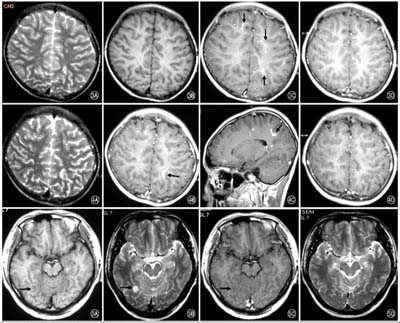

Phần lớn các trường hợp nhiễm Angiostrongylus cantonensis có hình ảnh tổn thương khá rõ, song không điển hình cho một bệnh lý nào, tuy nhiên nếu kết hợp một số xét nghiệm khác như công thức bạch cầu, huyết thanh miễn dịch có thể cho chẩn đoán thấu đáo hơn. Trên hình ảnh lát cắt của phim chụp CT_Scanner hoặc MRI cho các hình ảnh nốt canxi hóa, vôi hóa trong nhu mô não, rãnh não,…